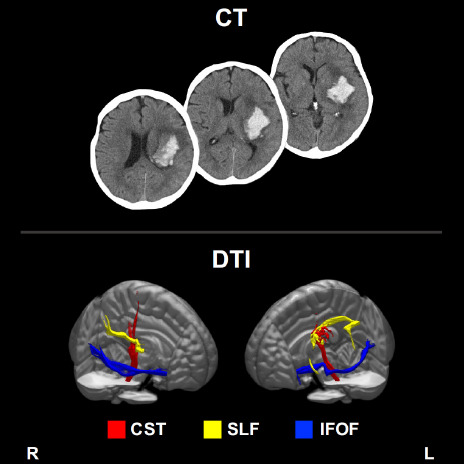

Methods: This study enrolled stroke patients, and diffusion-tensor imaging was conducted during the second week. Standardized automated tractography was utilized to compute FA values in the corticospinal tract (CST), the inferior fronto-occipital fasciculus (IFOF), and the superior longitudinal fasciculus (SLF). Outcome evaluations were performed at discharge from our affiliated rehabilitation facility. Extremity functions were assessed using the total scores of the motor component of the Stroke Impairment Assessment Set (SIAS-motor). Independence levels in ADL were appraised through the motor and cognition components of the Functional Independence Measure (FIM). For each outcome measure, multivariate regression analysis incorporated the FA values of the CST, the IFOF, and the SLF, along with age.

Results: Forty-two patients were enrolled in the final analytical database. Among the four explanatory variables, the CST emerged as the most influential factor for SIAS-motor scores. Conversely, age proved to be the primary determinant for both the motor and cognition components of FIM, surpassing the impact of FA metrics, including the CST and the IFOF.